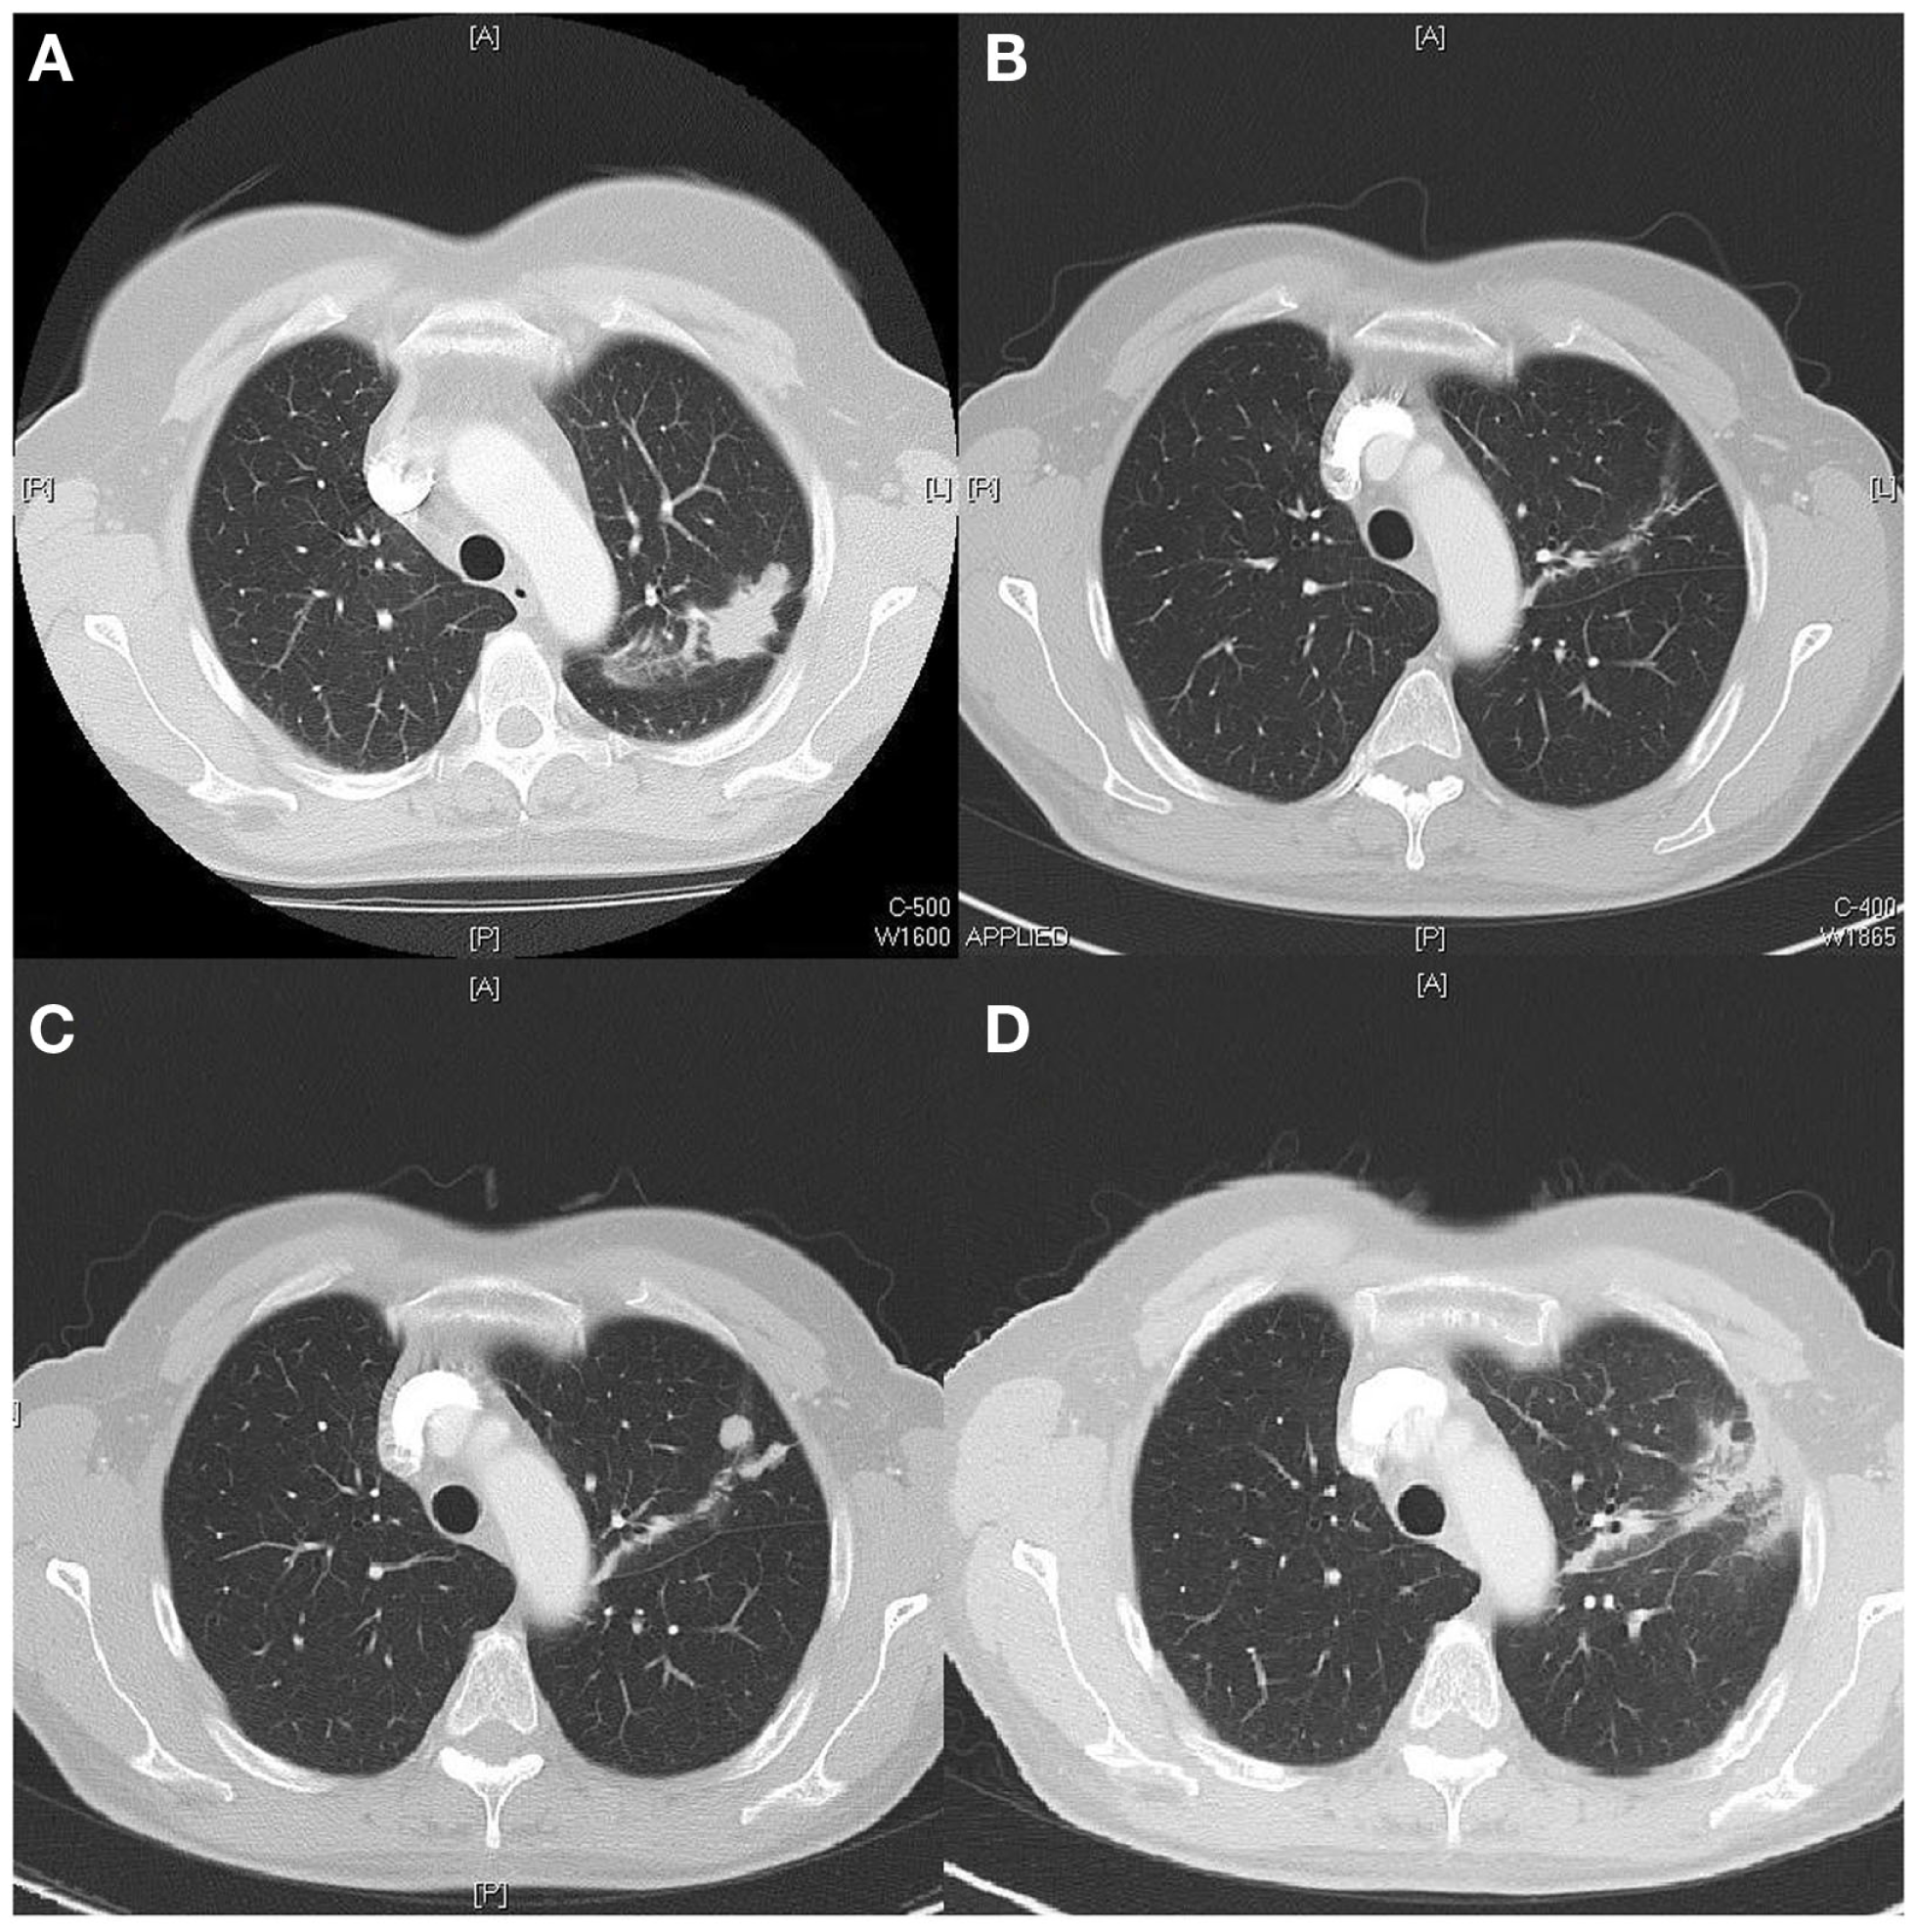

The first case concerns a 56 years old woman with a smoking history of 19 pack years (PY). In October 2011, she was diagnosed with a metastatic adenocarcinoma of the lung, epidermal growth factor receptor (EGFR) mutation positive with a deletion found on exon 19. The primary tumor was located in the left upper lobe (Figure 1A). There was a pericardial effusion that was proven to be metastatic.

Figure 1

(A) Tumor upper left lobe on diagnosis (CT scan). (B) Near complete response 2 months after start TKI (CT scan). (C) Local progression 18 months after diagnosis (CT scan). (D) Partial response 3 months after local stereotactic radiotherapy (CT scan).

In December 2011, the tyrosine kinase inhibitor (TKI) gefitinib (Iressa®) was started. The first follow up CT scan, 2 months after starting Iressa showed near complete response (Figure 1B).

In March 2013, 18 months after initial diagnosis, local progression is documented on the site of the primary tumor (Figure 1C) and staging by PET-CT showed no metastatic lesions. On the multidisciplinary oncology board, it was decided to give local stereotactic body radiotherapy (3 Gy × 20 Gy), which was started in April 2013. TKI treatment was temporarily stopped during radiotherapy. Three months after treatment a significant decrease of the tumor was seen (Figure 1D). Until October 2014, 17 months after completion of the radiotherapy, there is no evidence of disease and the patient continues TKI treatment.